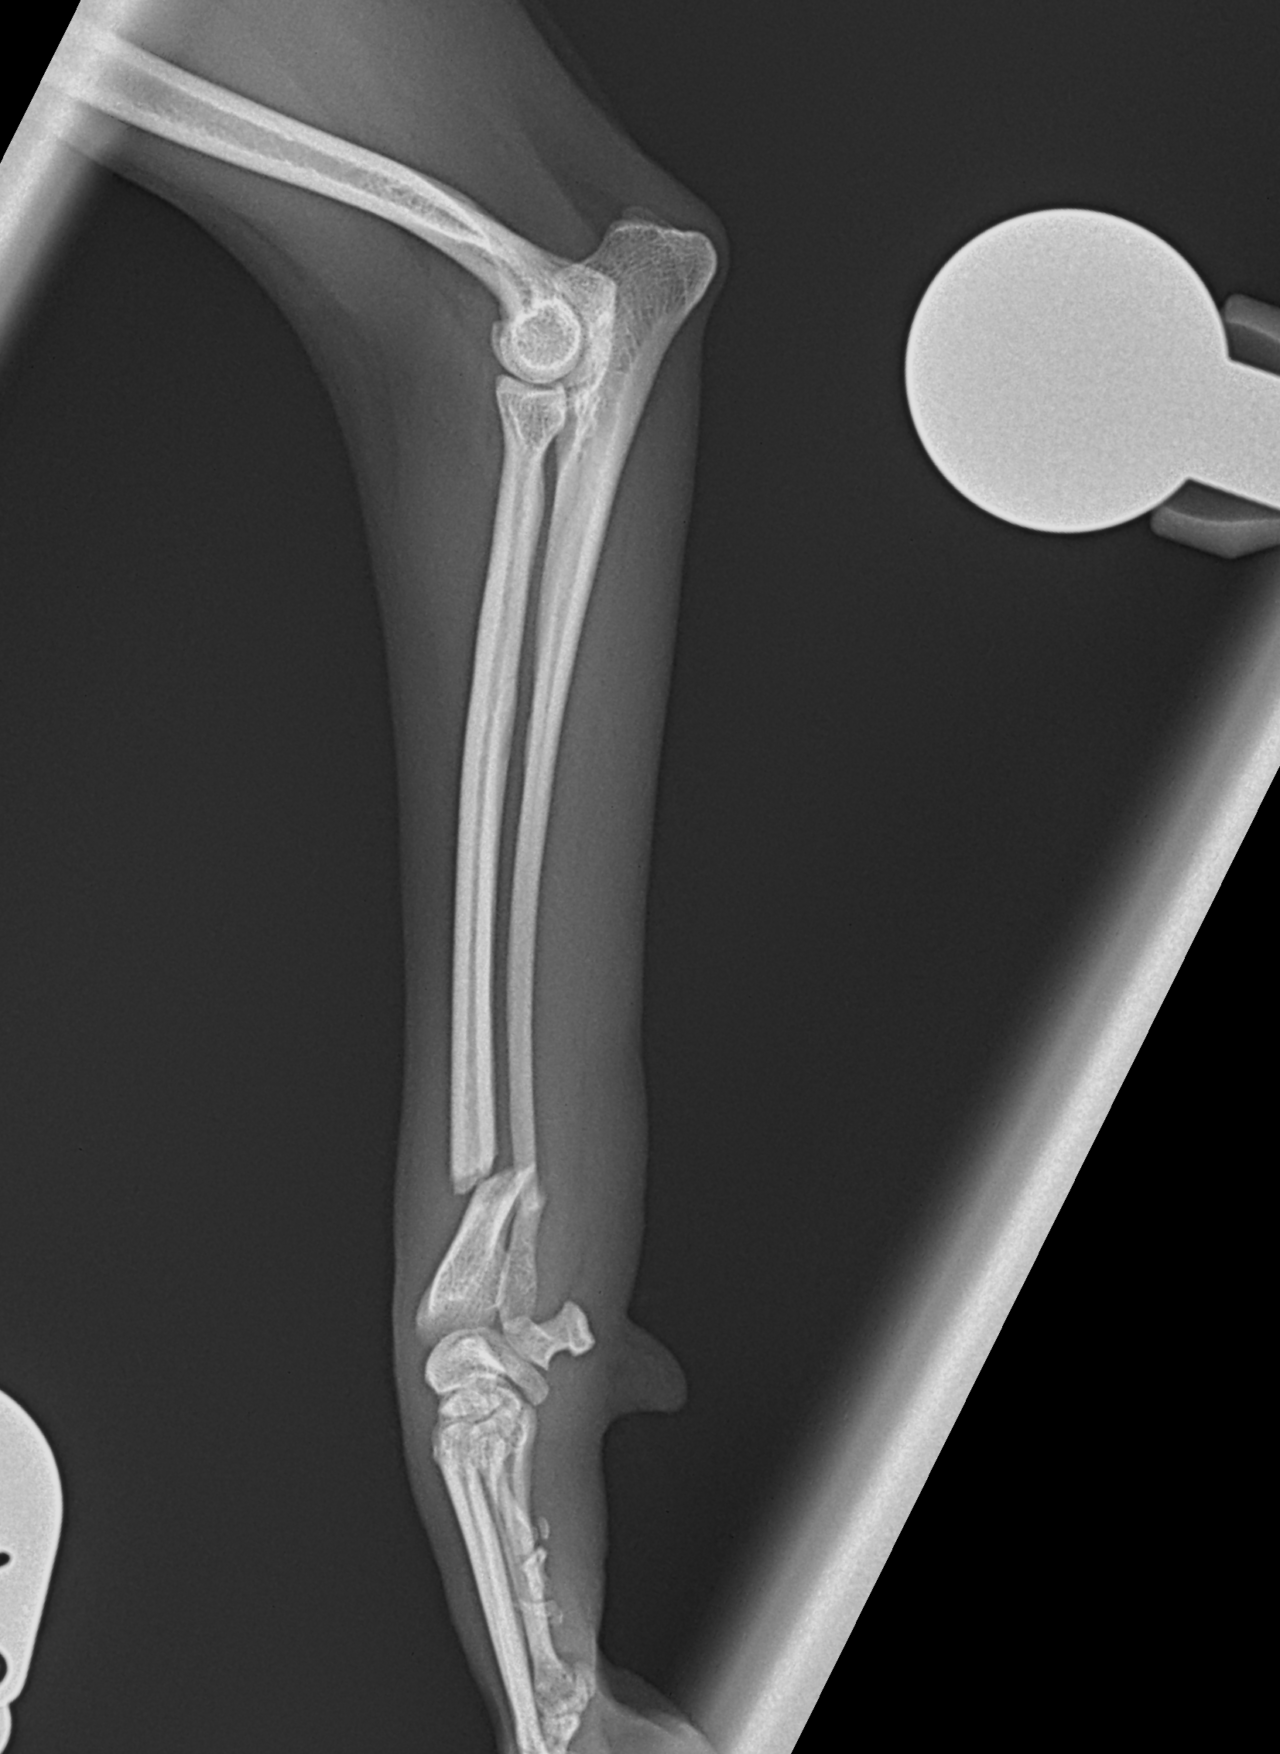

Tea Cup Poodleさんが、ご家族が家に帰宅すると足を挙上しており、着地できないとの事。室内で転倒したか、ソファーなどからジャンプして着地に失敗した可能性があります。エックス線検査で橈骨遠位端骨折が確定されました。1.5mm 3hole タイト ピッチ ストレートプレートで遠位端を固定しました。しばらくは安静が必要です。